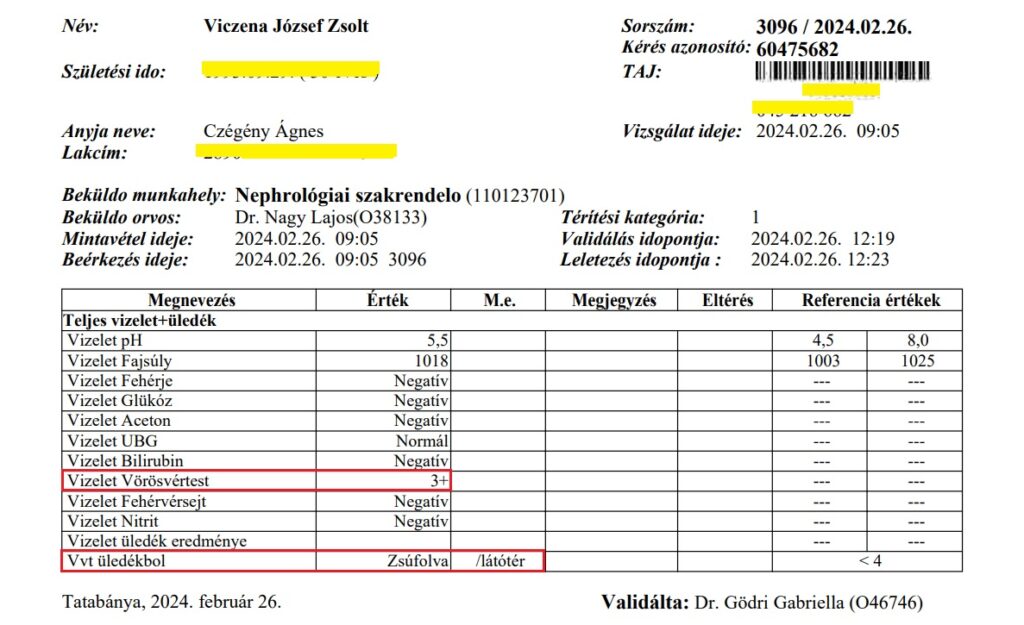

A vesekőzúzást (ESWL) tágult, gyulladt vesén végezték. Az operációnál, mert hogy ez annak számít, nem volt jelen az orvos! (De később a papírt kiküldte Dr Mosonyi Péter egy kolléganőjével az orvosi szobából, ekkor már operatőrként aláírva!) Ezért a technikus és a nővér tanácstalanok voltak, mit tegyenek egy ilyen gyulladt, tágult vesével, amit ultrahanggal láttak, elvégezzék-e a beavatkozást. Végül a kőzúzás mellett döntöttek. A fiam veséje az egyik legnagyobb mennyiséget, 3000-es ütésszámot kapta! Három hét múlva a fiam észrevette, hogy vérvizelése van. Odaadta az edényt, hogy vigyem le a háziorvosához, Dr Reisz Kornéliához, hogy adjon egy beutalót rá, hogy gyorsan le tudjuk adni. Megtagadta a beutalót, azt mondta, majd az asszisztens tesztcsíkkal megnézi. Aki pedig azt állapította meg, hogy „nincs benne vér, picike fehérje, de vér nincs.” A fiam otthon felrobbant a hülyének nézéstől, felöltözött és a már akkor is rossz állapotában maga vitte el a tatabányai Synlab-hoz leadni ugyanezt a vizeletet. A „nincs vér” igazából 3 keresztes vérvizelés és 100-szoros vörösvörtest/látótér volt. Már ekkor elkezdődött az, amiből aztán ahogy a cikk címe is utal rá, egy horrortörténet lett!

6./ Február 26-án Zsolt megcsináltatta Nagy Lajos alap vizeletvizsgálatát. Az eredmény?

3 keresztes vérvizelés és az üledékben „zsúfolt vörösvértest/látótér” vagyis maximális értéken a vérvizelés, de kristály sehol a vizeletben – amire Dr Nagy Lajos rá akarta fogni fiam aránytalanul súlyos állapotát- Jókorát tévedett a gerinc diagnózissal (bár sejtjük, szándékos „verbális játszma” volt, mint az EESZT-ből kiszedett magánvizsgálat leletével is) és a kristályokra fogott ambuláns véleményével. Az eredmény és történtek után a fiam már nem ment vissza többé ehhez az orvoshoz. Közben a kezeletlen vesemedence-gyulladás, vesemedence-fertőzés nem állt meg, dolgozott tovább háborítatlanul.